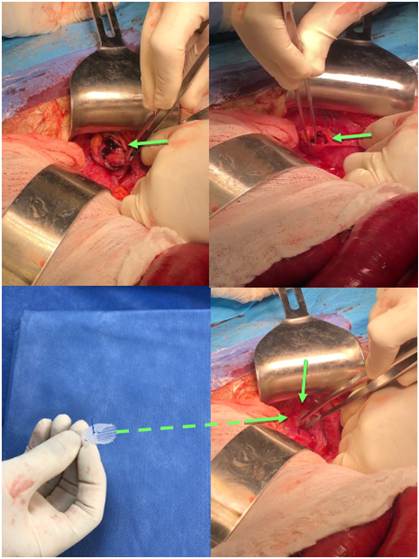

Tratamiento y técnica quirúrgica

Solo el 21,5 al 31,3% de pacientes con hernia obturatriz son diagnosticados correctamente antes de la cirugía 4. Generalmente, la obstrucción intestinal es la que motiva el tratamiento quirúrgico, por lo que los pacientes son llevados a laparotomía exploratoria, con hallazgos intraoperatorio de hernia obturatriz incarcerada (Figura 7), asociada o no a necrosis del intestino delgado, acorde al tiempo de evolución, lo que obliga a practicar resección intestinal con anastomosis 13,19,31. Aunque la vía laparoscópica ha venido aumentando su participación en el estudio de dolores pélvicos crónicos y resolución de las hernias con buenos resultados 32-34, no ha sido abiertamente aceptada para hernia obturatriz debido a su mayor tiempo operatorio y alto costo 10, a pesar de que un reciente estudio demostró que no hay diferencias significativas en el tiempo de cirugía laparoscópica versus vía abierta, y posee estancias hospitalarias menores, además de menos complicaciones y mortalidad 35,36.

- Laparotomía: es el procedimiento tradicional. La incisión mediana infraumbilical es la preferida en cirugía de urgencias con alta sospecha de estrangulación o necrosis intestinal, cuyas ventajas residen en la obtención de una mejor exposición del campo de visión sobre el saco herniario, la posibilidad de generar un diagnóstico definitivo, además de realizar una resección intestinal con anastomosis, si es necesario 10,17,36-41. Se inicia con la incisión infraumbilical mediana, se continúa la exploración sistemática del intestino para descubrir el asa incarcerada en el conducto obturador, utilizando pinza atraumática para evitar la apertura accidental del intestino, con salida de material contaminante 7.

La técnica del tapón con malla (Figura 8) necesita una adecuada calibración y ha logrado menos complicaciones de compresión del paquete neurovascular, tales como neuralgias difíciles de tratar 12, rechazo a cuerpo extraño y recurrencia herniaria. Algunos autores fijan la malla al ligamento de Cooper y al músculo obturador interno 40 y otros no la fijan 41.